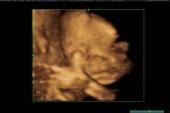

- 1、胎心率评价是通过识别胎心率的模式来评估胎儿情况,胎心率的模式反映胎儿的健康状况,和胎儿和新生儿的预后有关。2、胎心率描记:基线胎心率,加速,反应性,减速,宫缩频率。3、细胞凋亡主要发生在胚胎心脏

- 1、结论羊水细胞培养进行产前诊断是十分安全而可靠的.2、孕妇血浆中游离胎儿DNA可以用于无创伤产前诊断。3、目的:探讨彩色多普勒超声产前诊断多囊肾的临床价值。4、目的探讨胎儿脉络丛囊肿产前诊断的临床